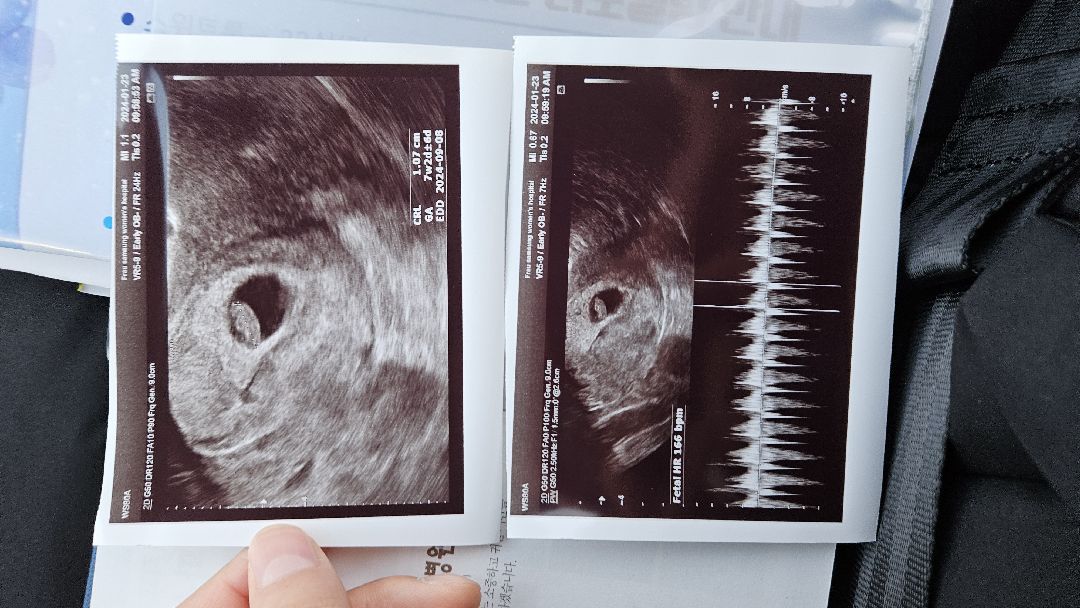

어플상 6주4일, 병원상 7주2일(첫 심장소리 청취완💕)

어플상 6주4일이랬는데 방금 병원 들렀다가니 7주2일, 아기가 1cm래요! (1.07) 심장소리 166이고 엄청 힘차더라구요! 와..산전검사 하고 가랬는데(소변, 피검) 보건소랑 똑같은건줄 알았는데 아니라네요? 보건소는 간단한 빈혈이나 이런것만 나온다고; 하는게 좋대서 했는데 비급여..155,000원정도 나왔어요ㅠ 9월 만출까지 다들 파이팅~!!! * 2주뒤 방문하라고 하셨고 어느정도 젤리곰 형태로 보이게되면 확정 분만 예정일 잡아주신다고 하셨어요ㅎㅎ